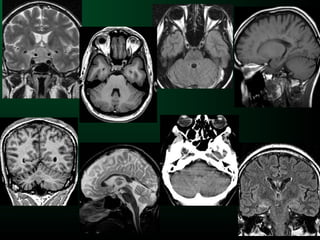

Pathologie tumorale intracrâniennePathologie tumorale intracrânienne

SémiologieSémiologie

• Topographie lésionnelle

• Œdème/Infiltration

• Prise de contraste et rupture de la BHE

• Nécrose centro-tumorale

• Effet de masse

• Engagement

Topographie lésionnelle

Intra-axiale Extra-axiale

Intra ou extra-axiale ?

Possible

– Base d’implantation large

– Modifications osseuses

– Rehaussement méningé

– Éloignement du cerveau /

crâne

Certain

– LCS entre cerveau et tumeur

– Cortex entre lésion et SB

– Vaisseaux entre les 2

Œdème péri-tumoral (vasogénique)

Hyposignal T1 / hypersignal T2

Limité par le corps calleux et les fibres en U

Aspects en « doigts de gants »

Nécrose centro-tumorale

Tumeurs de haut grade

Nécrose non hémorragique : Hypo T1, Hyper T2

Prise de contraste

Traduit souvent la malignité des tumeurs intra-parenchymateuses

2 mécanismes

– Rupture de la BHE

– néovascularisation

Lymphome Glioblastome